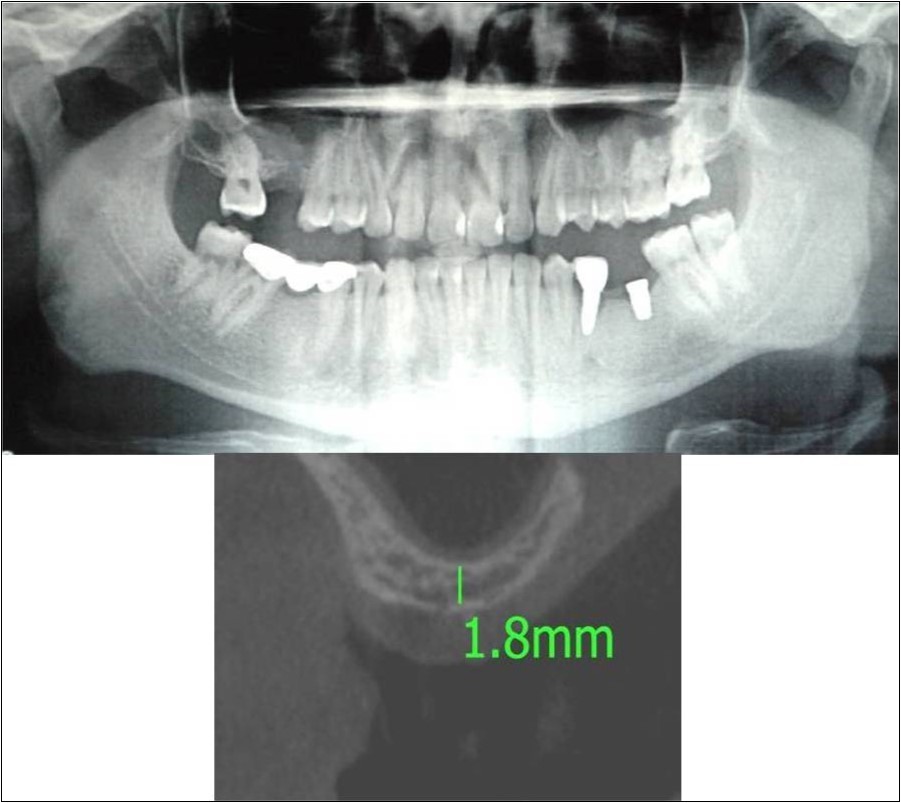

Clinical and Radiological Assessment:

3.Height of available bone- 1.8mm;

Treatment:

Patient underwent the procedure of direct sinus elevation using sinus lateral approach kit. After crestal and vertical release incisions, muco-periosteal flap was raised to expose the buttress region. A bony window of 1cm diameter was created; sinus lining identified and elevated up to receive calcium phosphosilicate as graft material and closure was achieved under local anaesthesia and strict aseptic protocols. Implant placement was planned to be carried-out after a period of 6 months to allow for the consolidation for graft and naive bone formation. At the end of 6 months, a repeat CBCT scan was advised to evaluate the increase in bone height. (Figure 17a,b, pre-treatment; Figure 18a,b, post-treatment)

Figure 17.a,b. Pre-treatment OPG and cross section of CBCT showing residual alveolar bone height for Case No.6;